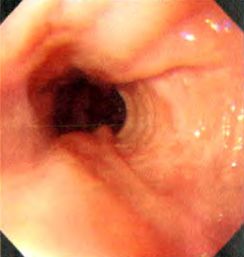

病例资料 患者,男,54岁,因“进食后腹胀伴暖气、返酸1月余,进食哽咽感2周”入院。起病以来,午后发热,在37.5℃~38.5℃之间波动,无腹痛、腹泻、胸闷及胸痛等表现。当地医院就诊,胸部CT平扫未见异常:胃镜提示:食管距中切牙36 cm至贲门齿状线可见一 1.0 cm×2.0 cm溃疡型肿块,表面污秽,呈结节状,活检质脆,易出血,考虑食管癌可能:病理示食管黏膜慢性炎性反应伴少量炎性坏死渗出物。患者至上海某医院就诊,再次行胃镜检查.提示距中切牙35~39 cm,溃疡新生物,病理提示:食管鳞形上皮及炎性肉芽肿组织。近2周来,患者出现进食后哽咽感,以进固体食物时明显。至我院就诊,行胸部增强CT示,食管下段管壁增厚,符合恶性肿瘤改变;胃镜示,食管距中切牙35~39 cm前壁左侧见黏膜隆起,表面高低不平,溃疡形成,质硬,易出血,见图1。超声胃镜示,局部食管壁各层结构消失,考虑食管恶性肿瘤,见图2。但病理示:食管鳞形上皮轻度增生,并见炎性肉芽组织和炎性渗出坏死物,符合炎性溃疡,见图3。遂行肠镜检查.提示回盲部溃疡,肠镜病理示炎性肉芽组织和炎性渗出坏死物,符合炎性溃疡,灶性区似有裂隙性溃疡,符合CD。综合考虑患者病史及各种辅助检查,诊断为:食管CD。

图3 食管组织病理图片符合炎性溃疡(苏木精.伊红染色.×100)